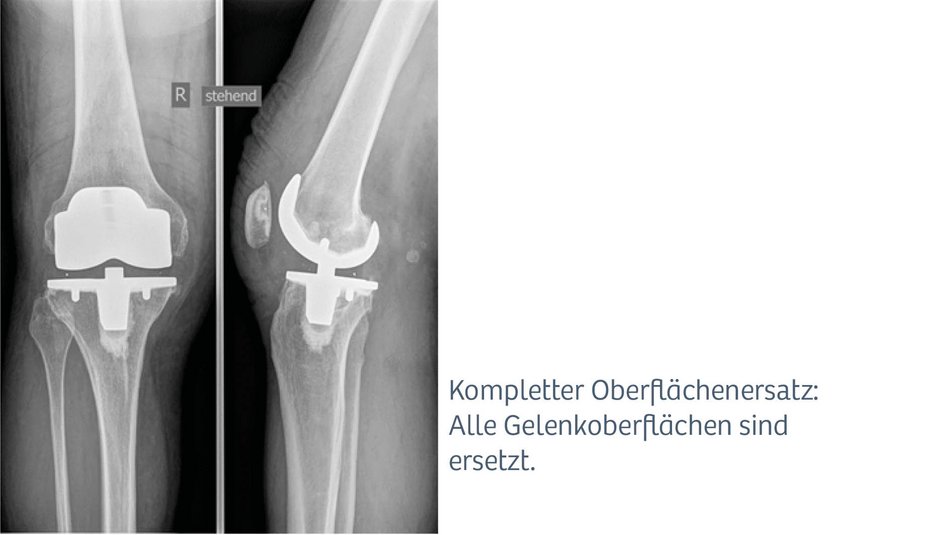

Kompletter Oberflächenersatz

Sind die Voraussetzungen für einen Teilgelenkersatz nicht mehr erfüllt, kommt der komplette Oberflächenersatz zur Anwendung. Es werden dabei alle Gelenkoberflächen ersetzt. Für Wechseloperationen, Instabilitäten, Deformitäten oder je nach Schwere der Erkrankung, werden unterschiedliche Prothesenmodelle vorgehalten.

In unserer Klinik kommen unterschiedlichste Knieprothesenmodelle standardmäßig zur Anwendung. Die am häufigsten verwendeten Knieprothesen sind der Teilgelenkersatz (Schlittenprothese), bei welchem nur eine Gelenkfläche ersetzt wird und der komplette Oberflächenersatz, bei welchem alle Gelenkflächen ersetzt werden. Wir greifen dabei auf ein großes Portfolio unterschiedlichster und bewährter Prothesenmodelle verschiedenster etablierter Hersteller zurück.